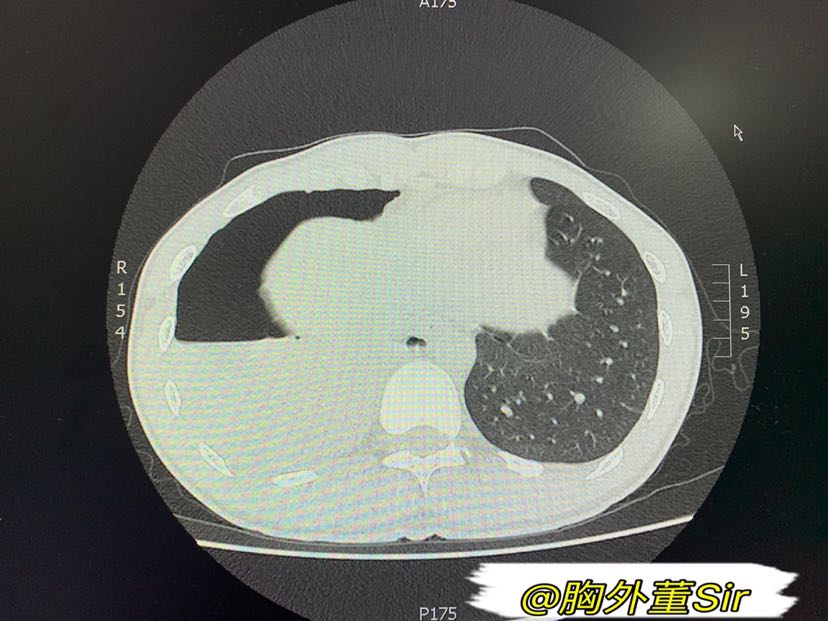

血气胸ct

【病例会诊】自发性血气胸

【影像读片】血气胸读片

自发性血气胸